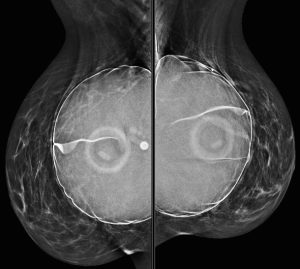

A 46-year-old woman presents with a tender and palpable left breast abnormality. A diagnostic mammogram is performed:

Explanation: These implants are filled with saline. Note the “see through” density of the saline, compared to the extremely dense silicone implant that was demonstrated in a previous case. We can also see the implant valves and mild rippling of the external implant contour, which are features typically associated with saline implants.

On the MLO images, we can see the pectoralis major wrapping around the anterior portion of the implant, which indicates that they are retropectoral implants (also known as “subpectoral”).